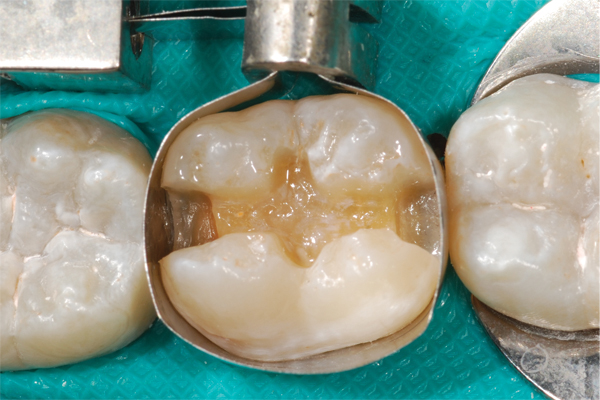

(3.) Restoration of tooth No. 31.

Figure 3

Higher viscosity bulk-fill composites can be used up to the occlusal surface, however. Two clinical cases using the bulk-fill composites Tetric EvoCeram Bulk Fill and SonicFill are presented in Figure 2 through Figure 6. Limitations when placing a high-viscosity bulk-fill composite include difficulty of condensing and esthetic restraints. Condensing a high-viscosity resin composite ensures adequate adaptation to the tooth preparation and sufficient interproximal contacts. Condensing 4 mm of composite is more difficult than condensing 2 mm. To ensure adequate interproximal contacts, a sectional or circumferential matrix with an inciso-gingival curvature can be used to obtain a tight area of contact gingival to the marginal ridge. A ring should be used to help separate the teeth and improve the tightness of the contact area.